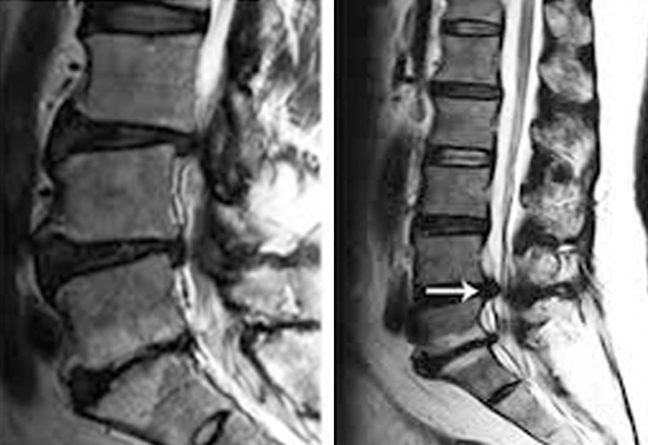

Αυτή η πίεση όταν διαρκέσει επί πολύ, αρχίζει να επιδρά στη σκληρότητα του οστού και όπως όταν το κτυπήσεις δημιουργεί οίδημα. Το οιδηματώδες αυτό κόκκαλο (οστούν) φαίνεται στην μαγνητική τομογραφία (λήψεις Τ2 και Stir) με άλλο χρώμα.

Αυτό ονομάζεται Μodic και εκφράζεται παθολογικά με βαθύ πόνο στη μέση μετά κόπωση και στο κρεβάτι στην ανάπαυση.